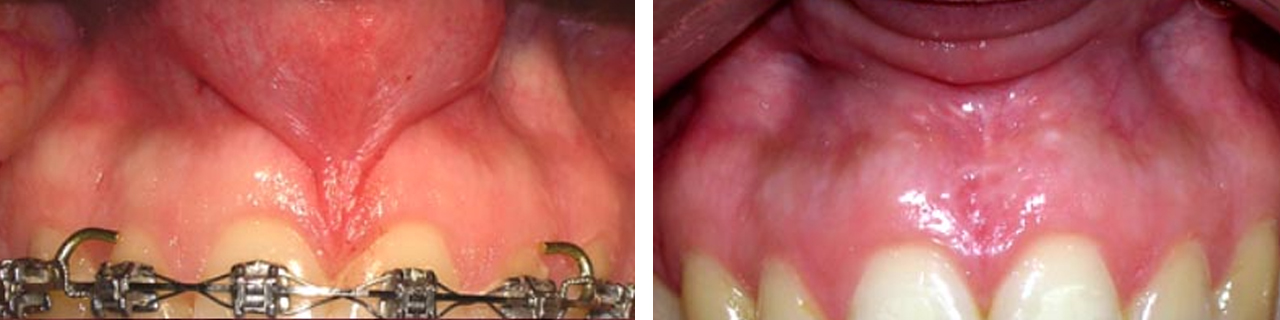

Frenillos

Eliminación de frenillos.